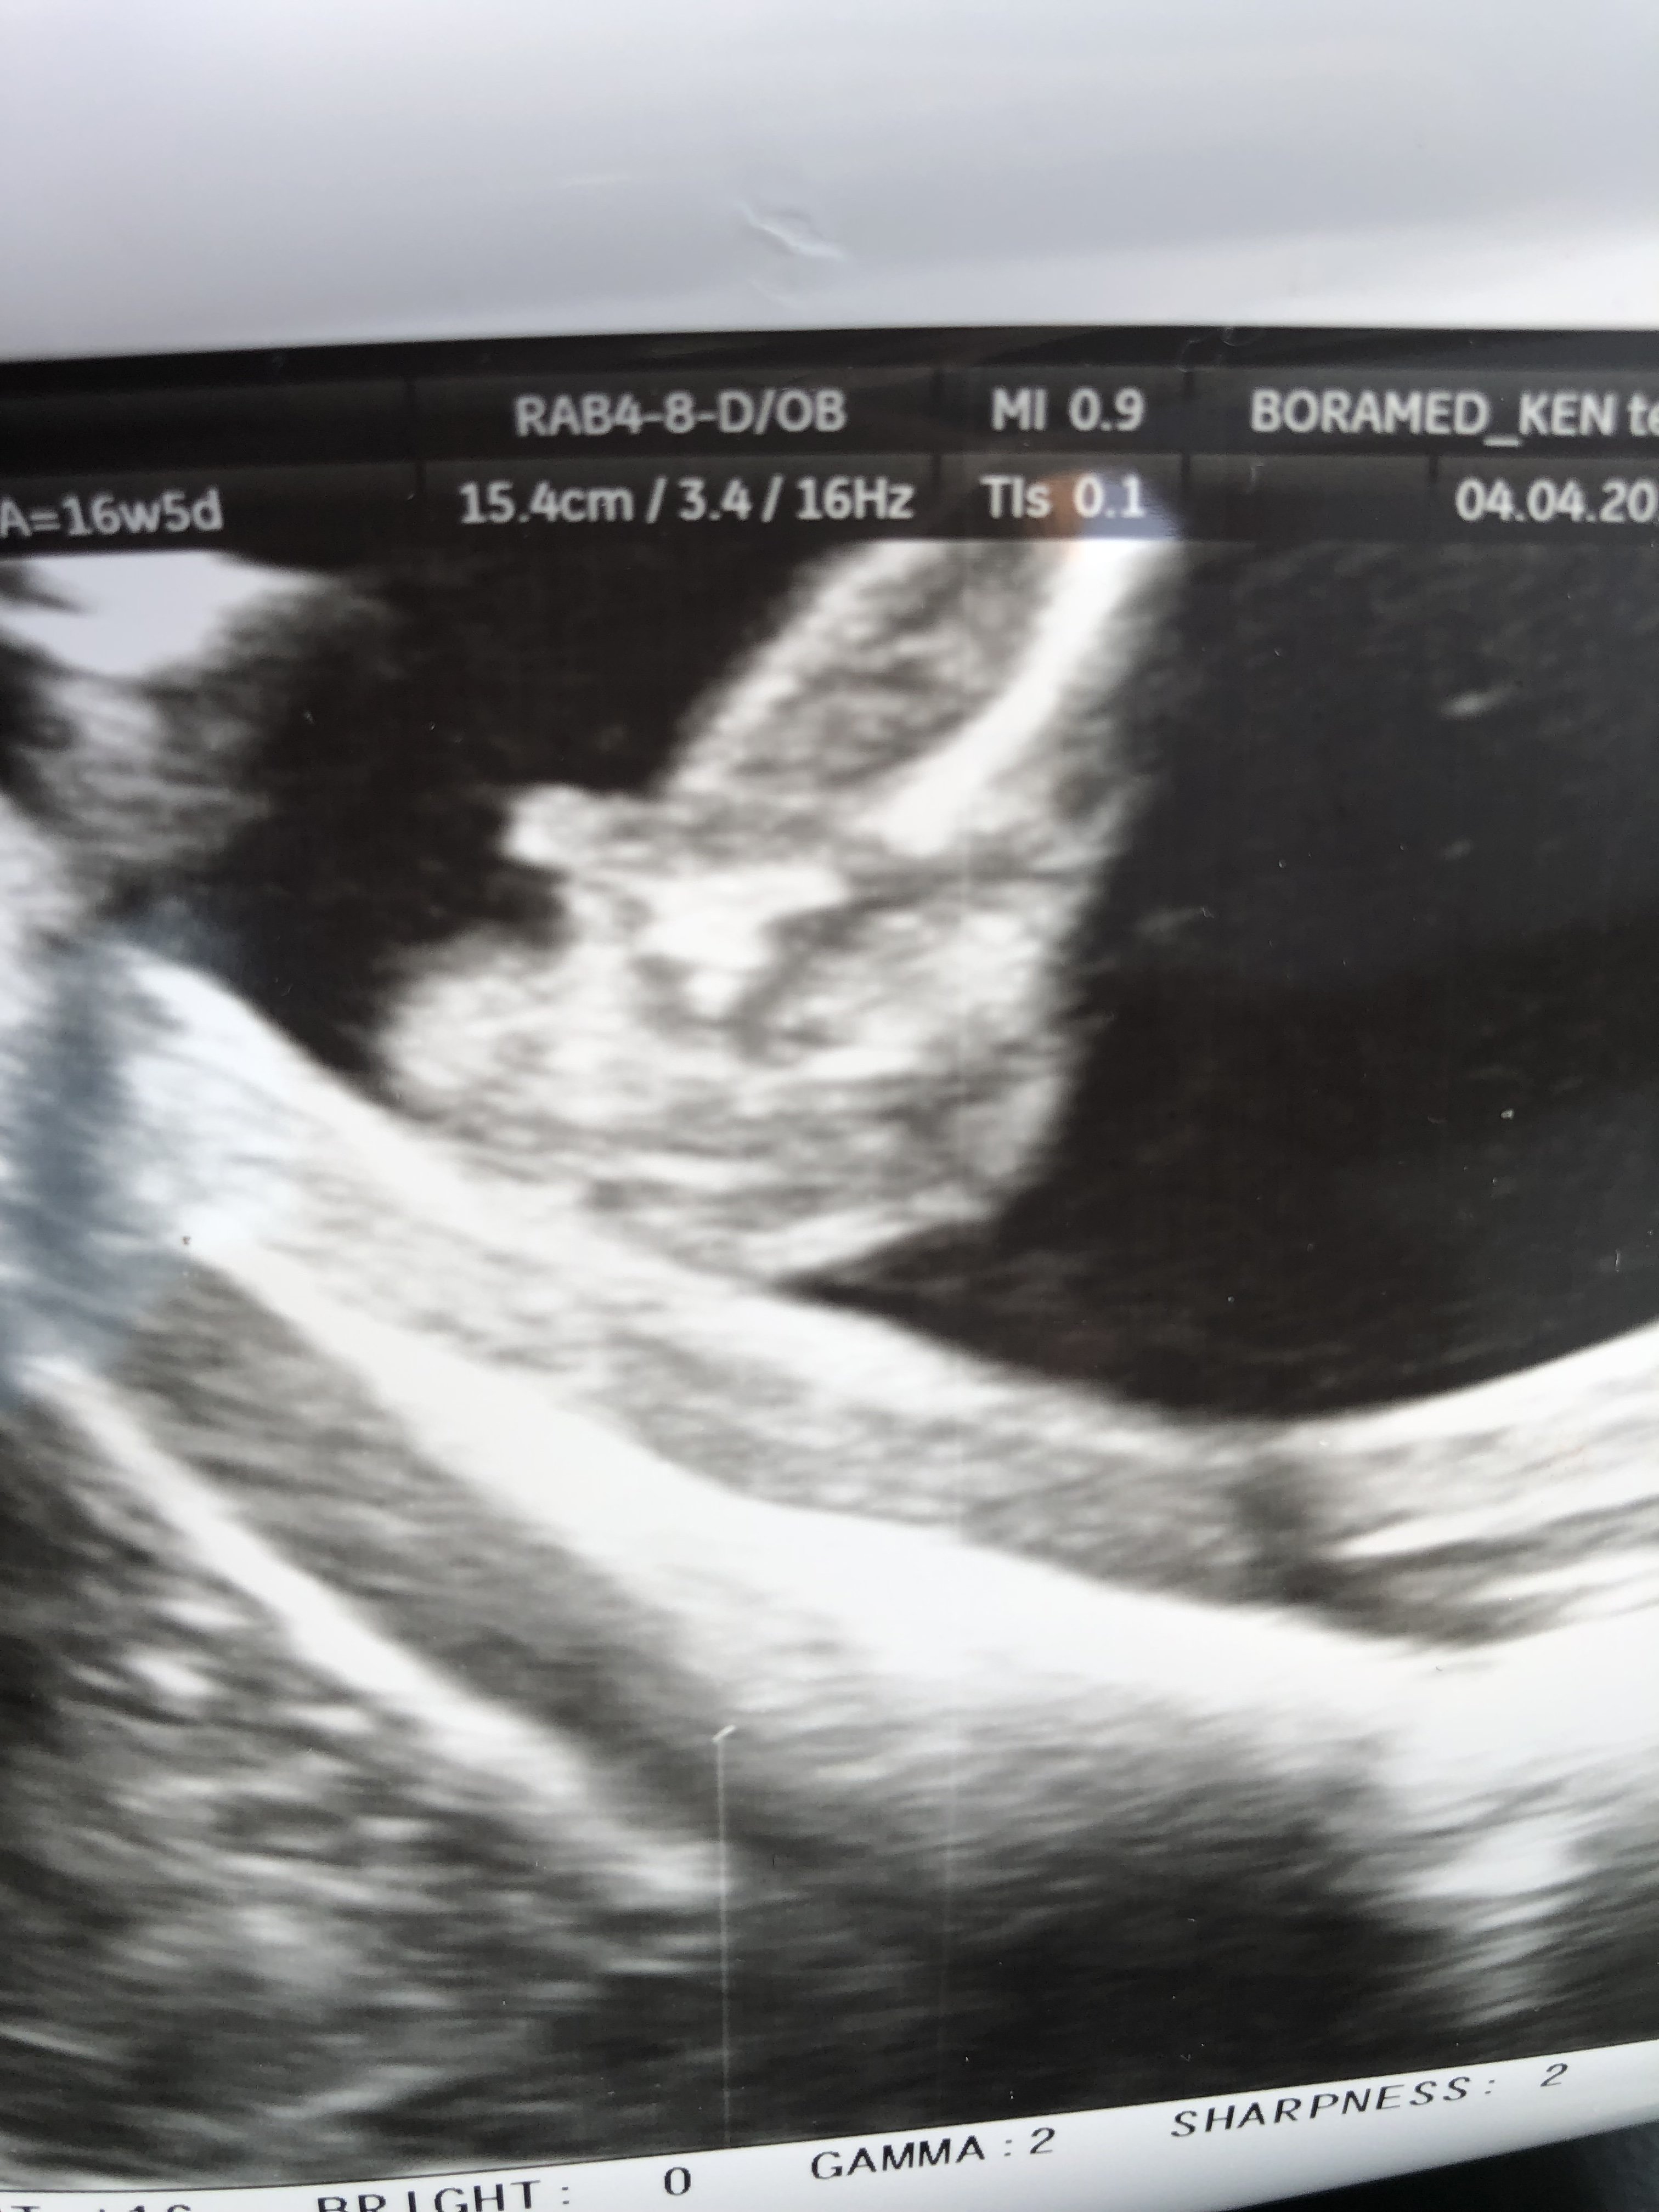

Karmelowe 14tc to już stanowczo za późno na potrzebie z nuba. Teraz idź po 16tc i niech zrobi potty shot.

A tak na serio to nadal masz 50/50 teraz widzę że u ciebie może być stacking ale nie jestem pewna czy widać tam całego nuba. Więc może to też być chlopczyk;)

Z nubami to teraz jest z 60-70% trafień